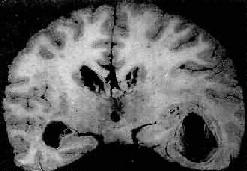

一、细菌性疾病(一)脑膜炎 脑膜炎(meningitis)可累有硬脑膜、蛛网膜和软脑膜。硬脑膜炎(pachymeningitis)多继发于颅骨感染。自从抗生素广泛应用以来,此病之发病率已大为减少。软脑膜炎包括蛛网膜和软脑膜炎症,则颇为常见。因此目前脑膜炎实际上是指软脑膜炎(leptomeningitis)而言。脑膜炎绝大部分由病原体引起,由脑膜炎双球菌引起的流行性脑膜炎是其中最主要的类型;少数则由刺激性化学药品(如普鲁卡因、氨甲蝶呤)引起。脑膜炎有3种基本类型:化脓性脑膜炎,淋巴细胞性脑膜炎(多由病毒引起),慢性脑膜炎(可由结核杆菌、梅毒螺旋体、布氏杆菌及真菌引起)。本节重点叙述化脓性脑膜炎。 1.急性化脓性脑膜炎急性化脓性脑膜炎是软脑膜的急性炎症,大量炎性渗出物积聚于蛛网膜下腔。其中流行性脑膜炎多在冬春季流行,其余病原的脑膜炎则多为散发性。 【病因和发病机制】 急性化脓性脑膜炎的致病菌类型随患者之年龄而异。在青少年患者中以脑膜炎双球菌感染为主。该菌存在于病人和带菌者的鼻咽部,借飞沫经呼吸道传染,细菌进入上呼吸道后,大多数只引起局部炎症,成为健康带菌者;仅小部分机体抵抗力低下的患者,细菌可从上呼吸道粘膜侵入血流,并在血液中繁殖,到达脑脊膜后引起脑膜炎。在冬春季可形成流行,称为流行性脑膜炎。 新生儿脑膜炎最常见的病因是大肠杆菌,感染多来自产道。由于体内缺乏能中和病菌的IgM,入侵的大肠杆菌得以繁殖而致病。 流感杆菌脑膜炎多见于3岁以下之婴幼儿。肺炎球菌脑膜炎在幼儿和老年人常见,其中幼儿的脑膜感染多来自中耳炎,而在老人则常为大叶性肺炎的一种并发症。 【病理变化】 肉眼观,脑脊膜血管高度扩张充血,病变严重的区域,蛛网膜下腔充满灰黄色脓性渗出物,覆盖着脑沟脑回,以致结构模糊不清(图16-10),边缘病变较轻的区域,可见脓性渗出物沿血管分布。在渗出物较少的区域,软脑膜往往略带混浊。脓性渗出物可累及大脑凸面矢状窦附近或脑底部视神经交叉及邻近各池。由于炎性渗出物的阻塞,使脑脊液循环发生障碍,可引起不同程度的脑室扩张。

图16-10 化脓性脑膜炎 蛛网膜下腔内有多量脓液堆积以致大部分脑表面的沟回结构不清;脑膜血管高度扩张充血 镜下,蛛网膜血管高度扩张充血,蛛网膜下腔增宽,其中有大量中性粒细胞及纤维蛋白渗出和少量单核细胞、淋巴细胞浸润(图16-11)。用革兰染色,在细胞内外均可找到致病菌。脑膜及脑室附近脑组织小血管周围可见少量中性粒细胞浸润。病变严重者,动、静脉管壁可受累并进而发生脉管炎和血栓形成,从而导致脑实质的出血性梗死。